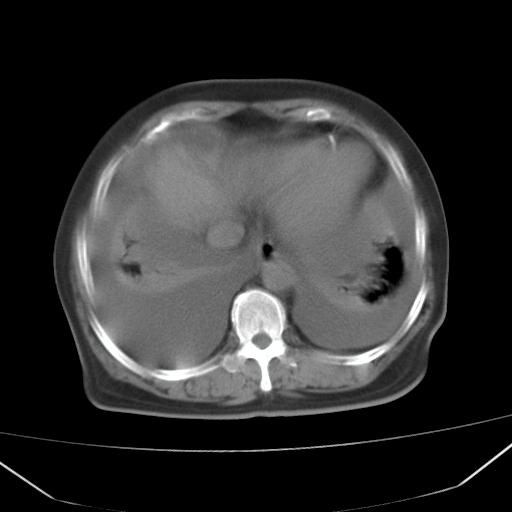

以下是引用jiangjing在2008-4-20 10:43:00的发言:[br]结合病史支持 冠心病[冠状动脉钙化],心功能不全,肺淤血、肺水肿,双侧胸腔与斜裂积液

以下是引用liuyue在2008-4-19 22:25:00的发言:[br]先考虑:1.心衰伴肺水肿、双侧胸腔积液、叶间积液、双下肺不完全性肺不张; [br] 2.冠状动脉粥样硬化。

以下是引用lijuanln在2008-4-19 23:05:00的发言:[br]两侧胸腔积液,肺水肿[br]心包积液[br]提示心衰